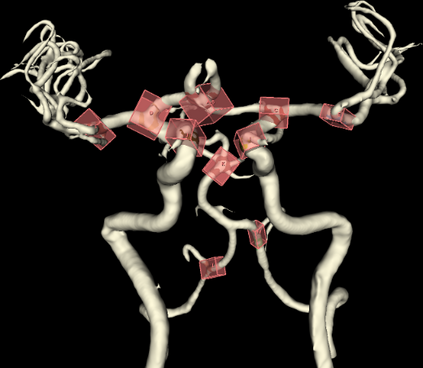

We hereby present a full synthetic model, able to mimic the various constituents of the cerebral vascular tree: the cerebral arteries, the bifurcations and the intracranial aneurysms. By building this model, our goal was to provide a substantial dataset of brain arteries which could be used by a 3D Convolutional Neural Network (CNN) to either segment or detect/recognize various vascular diseases (such as artery dissection/thrombosis) or even some portions of the cerebral vasculature, such as the bifurcations or aneurysms. In this study, we will particularly focus on Intra-Cranial Aneurysm (ICA) detection and segmentation. The cerebral aneurysms most often occur on a particular structure of the vascular tree named the Circle of Willis. Various studies have been conducted to detect and monitor the ICAs and those based on Deep Learning (DL) achieve the best performances. Specifically, in this work, we propose a full synthetic 3D model able to mimic the brain vasculature as acquired by Magnetic Resonance Angiography (MRA), and more particularly the Time Of Flight (TOF) principle. Among the various MRI modalities, the MRA-TOF allows to have a relatively good rendering of the blood vessels and is non-invasive (no contrast liquid injection). Our model has been designed to simultaneously mimic the arteries geometry, the ICA shape and the background noise. The geometry of the vascular tree is modeled thanks to an interpolation with 3D Spline functions, and the statistical properties of the background MRI noise is collected from MRA acquisitions and reproduced within the model. In this work, we thoroughly describe the synthetic vasculature model, we build up a neural network designed for ICA segmentation and detection, and finally, we carry out an in-depth evaluation of the performance gap gained thanks to the synthetic model data augmentation.